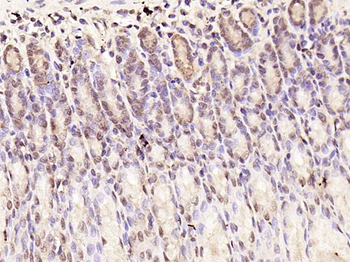

100 μl, 200 μl, 50 μlSMAD7 Rabbit Polyclonal Antibody [orb500819]

FC, ICC, IF, IHC-Fr, IHC-P, WB

Bovine, Porcine

Human, Mouse, Rat

Rabbit

Polyclonal

Unconjugated

100 μl, 200 μl, 50 μlPhospho-Smad3 (Ser213) Rabbit Polyclonal Antibody [orb106193]